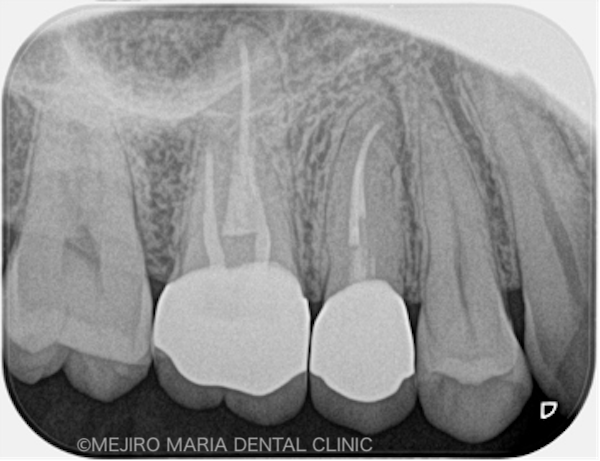

目白マリア歯科|ブログ|【症例】コンセプトを守った再根管治療(精密根管治療)|治療前後の比較画像

治療前の状態・主訴

患者様は、「数年前に虫歯治療した歯の、根元が腫れた」という主訴で来院されました。かかりつけ医に相談したところ、痛くないのであれば様子を見るようにと指示されましたが、不安を抱いて当院へお越しになりました。